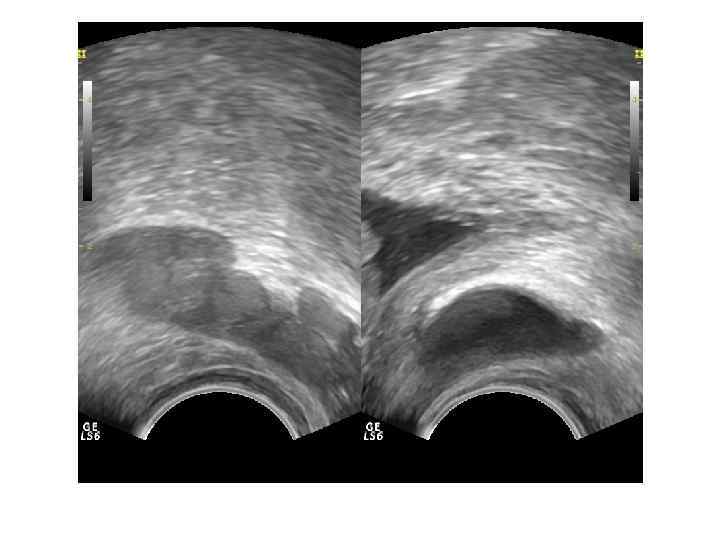

Для трансректального исследования (ТРУЗИ) простаты необходим полостной трансректальный датчик 7, 5— 10, 0 МГц. При ТРУЗИ возможно точное определение размеров и объема железы, выявление тонких структурных изменений и особенностей кровоснабжения паренхимы. Исследование позволяет детально оценить состояние железы при ДГПЖ, особенности роста аденоматозных узлов, состояние паренхимы и капсулы. Трансуретральное исследование простаты не имеет существенных преимуществ перед трансректальным при значительно более инвазивной технологии.

При ДГПЖ меняются форма, размеры, структура и соотношение частей железы. Форма становится шаровидной или неправильной с выбуханием контура в просвет мочевого пузыря. При росте переходных зон происходит значительное увеличение размеров, но это не приводит к выраженной обструкции уретры. При росте периуретральных желез простата увеличена незначительно, но происходит сдавление уретры выбухающей средней долей. Структура гиперплазированных узлов неоднородная, часто с дегенеративными изменениями ( кисты, участки склероза, кальцификаты).

ДГПЖ Доброкачественная гиперплазия простаты – заболевание , характеризующееся гиперплазией железистых и стромальных элементов ткани предстательной железы. Основными источниками ДГПЖ являются переходные зоны и зона периуретральных желез.

Если происходит преимущественный рост переходных зон, образуются латеральные доли. Зональная анатомия предстательной железы при ДГПЖ. При ДГПЖ увеличивается объем переходной зоны (Tz), размеры центральной зоны (Cz) и периферической зоны (Pz) уменьшаются. Vm — семенной бугорок, А — фибромускулярная строма.

При росте периуретральных желез (ограниченных препростатическим сфинктером) образуется средняя доля.